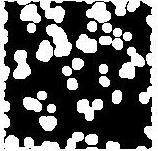

Inversion: Inversion is necessary in the work carried here since the counting operation is performs only on the for ground pixels, performing inversion which make easyforcellcountingjustbyInvertingtheclosing

Fig7:Invertedimage